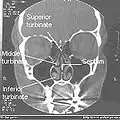

Coronal section of nasal cavities